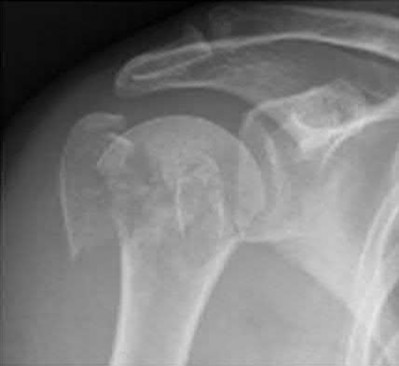

1036) A 68-year-old woman sustains the injury seen in Figure 189 following a fall. Careful neurologic and vascular examinations reveal no associated injury. What is the most common complication of surgical fixation with a locked plate and screw construct through a deltopectoral approach?

5. Screw penetration of the articular surface Corrent answer: 5

Several studies have documented screw penetration through the articular surface as the leading complication with locked plate and screw fixation for displaced proximal humerus fractures. Axillary nerve palsy is rare but can be seen with a deltoid split approach. Whereas some loss of range of shoulder motion is expected following this injury, infection rates about the shoulder are in the 1% to 5% range. While a portion of the deltoid insertion is commonly taken down, complete deltoid insertion detachment has not been described.